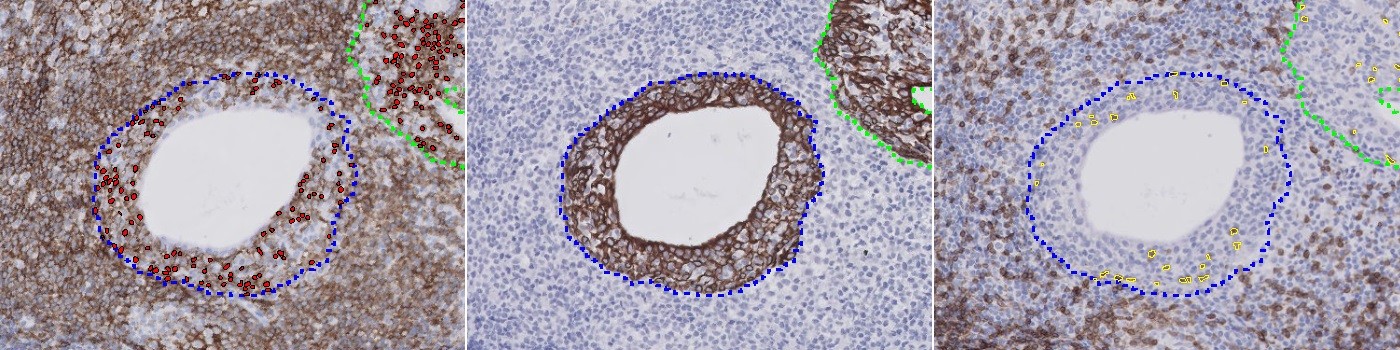

Evaluation of the lymphocytic infiltration is relevant in the study of the pathogenesis and outcome of Sjögren’s syndrome, see [1] and [2]. A manual evaluation of the infiltration is challenging, especially if it should be limited to the striated ducts of salivary gland tissue. This APP allows for automatic quantification of CD3 positive T-cells and CD20 positive B-cells within CK positive ducts.

Step 3: Run the “02 Duct Detection” APP which detects the salivary ducts.

Step 4: Run the “03 CD3 Quantification” APP which detects CD3 positive cells.

Step 5: Run the “04 CD20 Quantification” APP which detects CD20 positive cells.

The ducts are found by use of the HDAB-DAB color deconvolution band and an intensity-based threshold classifier. The configuration for quantification of CD3 positive cells works within the automatically outlined ducts. Detection of CD3 positivity is based on the HDAB-DAB color deconvolution band and separation of positive cells are based on application of a watershed algorithm assisted by a polynomial local linear filter applied to the red color band. The CD20 positive cells are detected by characterization of the stain in the cytoplasm of the cells based on the HDAB-DAB color deconvolution band. A polynomial blob filter and a polynomial local linear filter similar to that used for the CD3 cell quantification protocol assists the cytoplasm detection.